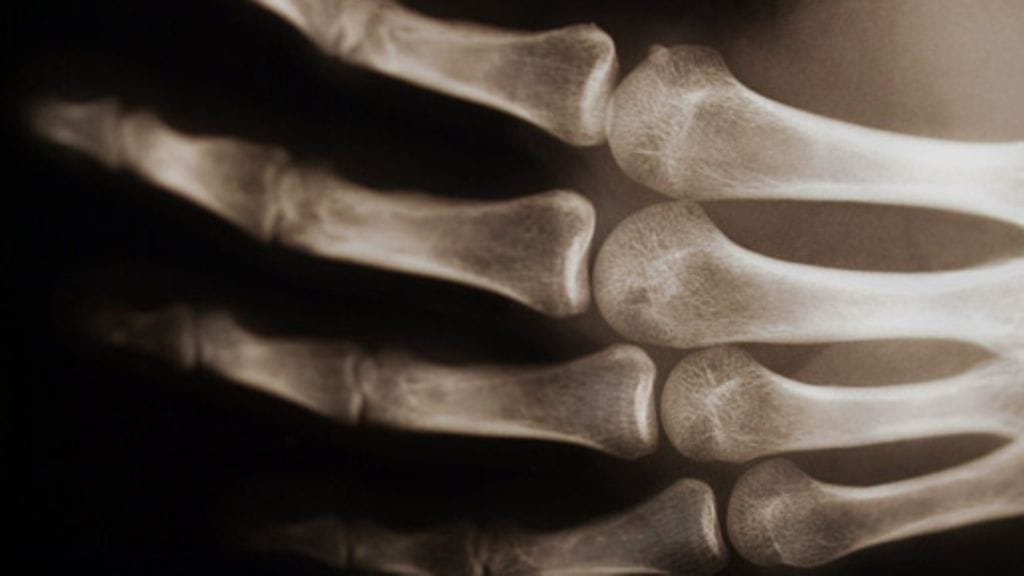

Vartalon tukirankana toimivan luuston hyvinvoinnin merkitys on kaikille ilmiselvä, mutta tiesitkö, että itse asiassa luusi alkavat haurastua jo varsin nuorella iällä? Peli ei kuitenkaan ole menetetty: luidensa vankistamiseen voi jokainen vaikuttaa varsin yksinkertaisin toimin.

Ihmisen luusto saavuttaa luutiheytensä huipun jo 25–30–vuoden iässä, jonka jälkeen luut alkavat vääjäämättömästi haurastua. Tätä rappeutumista voidaan vain hidastaa. Ratkaisevaa on, kuinka kestäväksi luut ovat lujittuneet ja kuinka niistä pidetään huolta käännekohdan jälkeen.